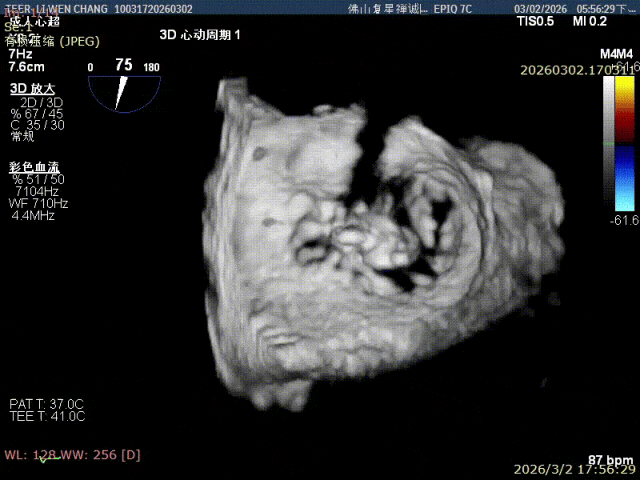

在夹子外侧补放一枚SN0409夹

外侧反流消失

组织桥稳定

反流减少至微量